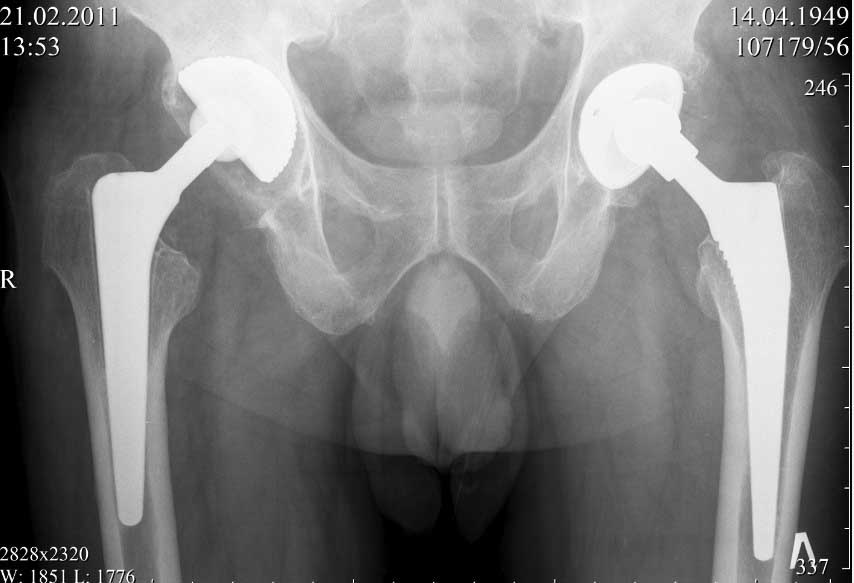

далее снимок у меня на приеме